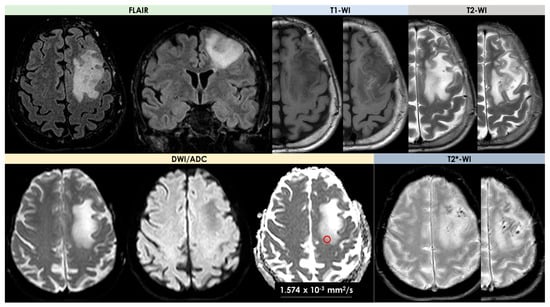

- Signal features: T1-Weighted Imaging (T1-WI) hypointense signal and intermediate to hyperintense signal on T2WI without diffusion restriction; intralesional microhemorrhages (small linear or punctate patterns on either Gradient Recalled Echo (GRE-T2*) or Susceptibility Weighted Imaging (SWI)) in 8/10 (80%) patients;

- Perilesional vasogenic edema (T2-WI high signal): marked in 5/10 (50%) patients and moderate in 5/5 10 (50%) patients;

- Enhancement patterns (parenchyma): all patients (10/10, 100%) had enhancing lesions with patchy parenchymal pattern in 5/10 (50%), “mottled appearance” (multiple small hypoenhancing areas within the patchy enhancing masses) in 3/10, small nodular pattern in 5/10, ring enhancement in 2/10, and linear (perivascular) enhancement pattern in 1/10 patients;

- Enhancement patterns (leptomeninges): localized leptomeningeal enhancement adjacent to the dominant/largest lesions was found in 4/10 patients (40%), localized subependymal enhancement adjacent to the lesions in 3/10 patients (30%); and diffuse leptomeningeal or subependymal enhancement was not documented;